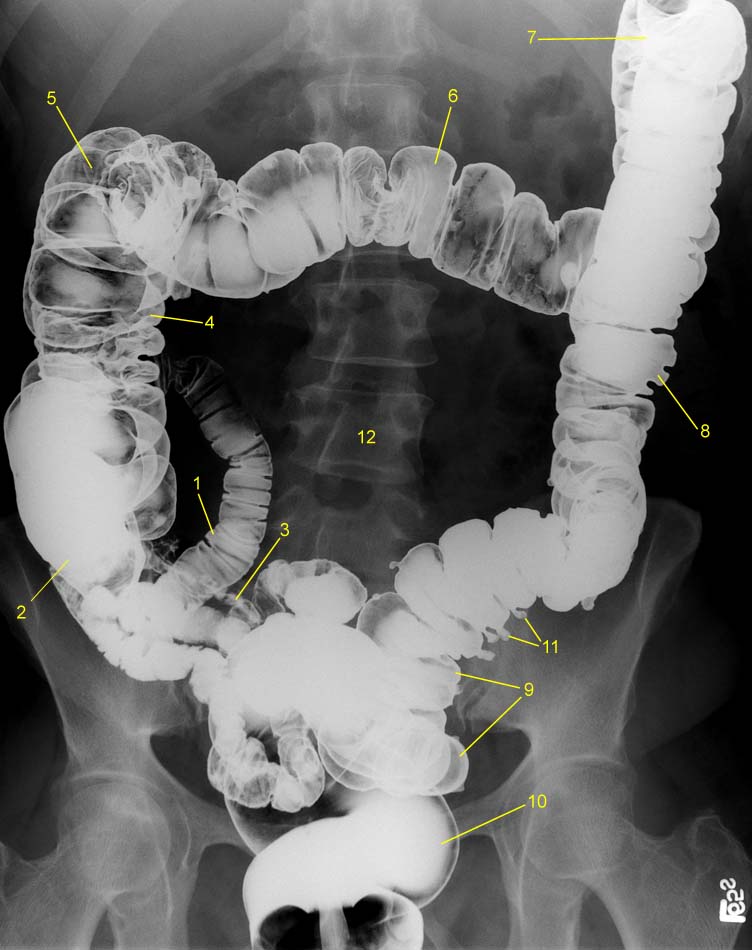

Рентгеноконтрастные Исследования Кишечника: Визуализация и Методики